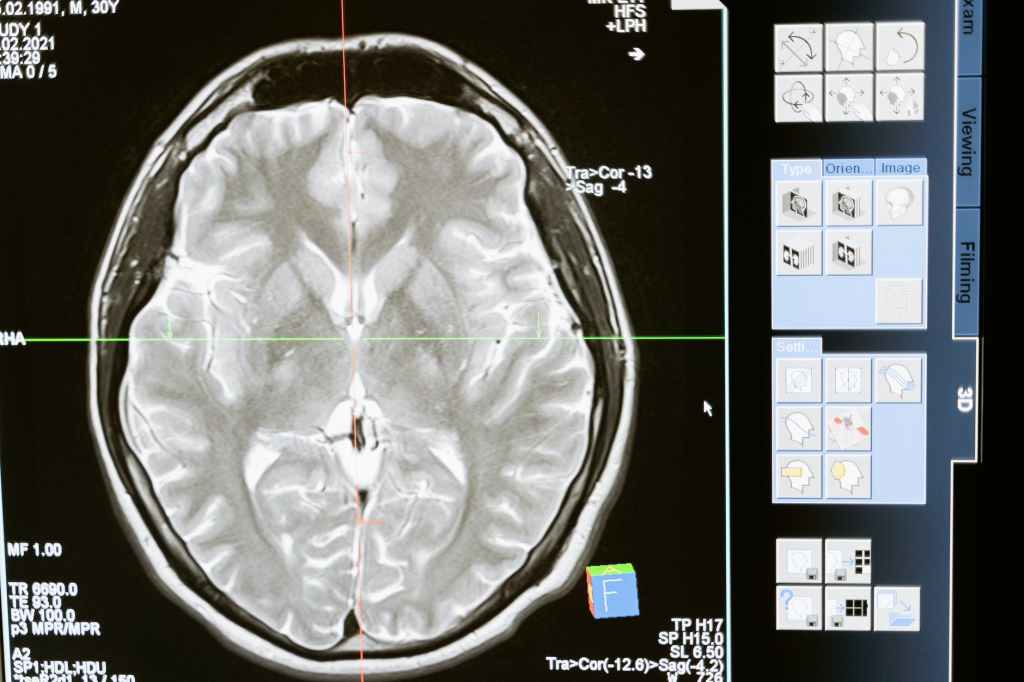

My dad was taken to the emergency room, where multiple tests revealed a cancerous brain tumor in his right frontal lobe. My brother and two sisters awaited every update. We hoped it was benign, something that could be removed without issue.

The doctors diagnosed his tumor as Glioblastoma, the most aggressive form of brain cancer. He couldn’t return home, nor could they treat him. Instead, he was referred to a team of specialists in Buffalo, NY.

The medical staff informed Marie that his regiment wasn’t working. The latest MRI results were in. His oncologist found another two lesions on his brain, and he wasn’t strong enough for anymore treatments.